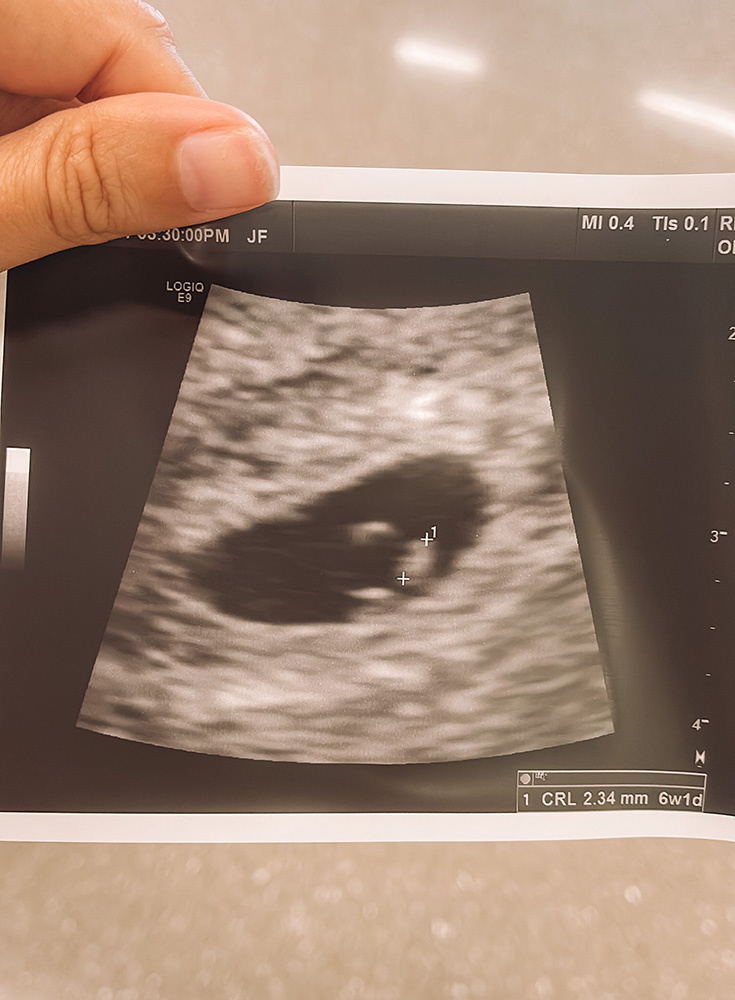

Typically, you’ll have your first prenatal appointment at 8 weeks. It can feel like an eternity waiting for this appt, but there isn’t anything to see on an ultrasound for a few weeks, so they wait until you are farther along to have your first appointment.

- Transvaginal Ultrasound: This is a wand-like tool that does an ultrasound inside of you.

- You should be able to see the yolk and sac and a tiny fetus at this appointment 🙂